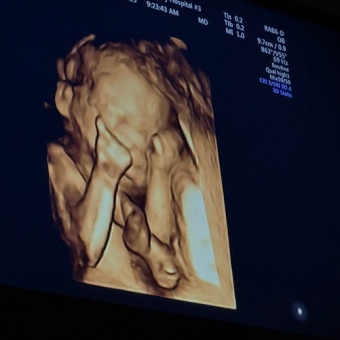

Baby Goose 🪿

Shelby & Daniel Goosherst

June 27, 2025

Hello everyone! Thank you for stopping by and joining us on this very special journey with our sweet baby boy.